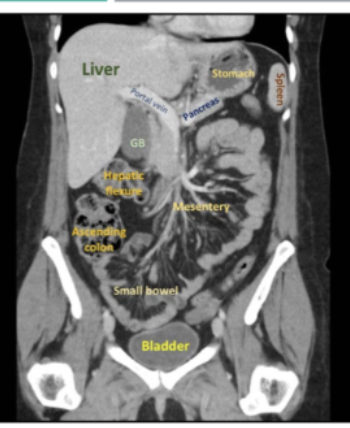

Orientation:

• patient is scanned in the SUPINE position.

• The patient’s right is on the viewer’s left, and the patient’s left is on the viewer’s right, which is a standard convention in medical imaging to maintain consistency.

• top of each image is the anterior (front)

• bottom is the posterior (back) part.